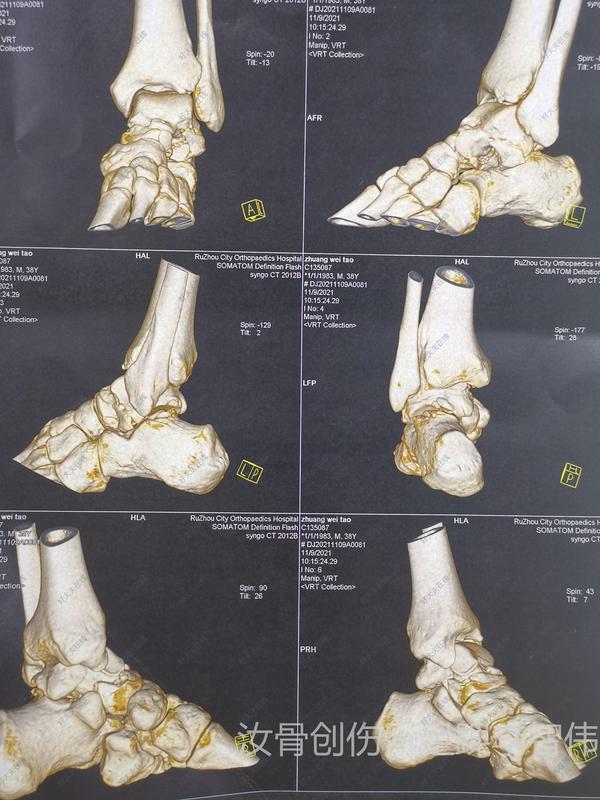

治療前 男,36歲,2米高墜落傷伴外翻損傷。致距骨頸骨折、距骨外側(cè)突撕脫性骨折(距腓前韌帶距骨附著處)。 治療中 踝關(guān)節(jié)外側(cè)切口,顯露距骨頸外側(cè)及距腓前韌帶距骨骨折塊。復(fù)位,克氏針臨時(shí)固定,無(wú)頭加壓釘+1枚掌骨板塑形后固定。 治療后 治療后7天 術(shù)中C臂透視位置可。 術(shù)后支具輔助下訓(xùn)練4周,4周后康復(fù)師指導(dǎo)下訓(xùn)練。 期待一個(gè)好的結(jié)果。